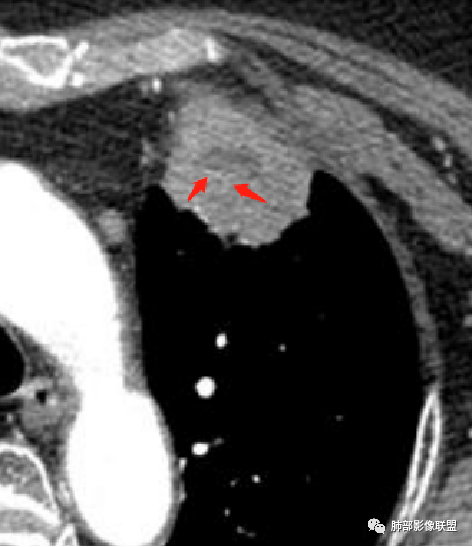

1、坏死区环形强化,指向慢性脓肿。

2、坏死区有血管,基本排除结核。

3、这个卫星灶,更进一步定了大方向,炎性。

※综上所述,看到这四幅图,基本能够准确诊断炎性※

3.病灶密度不均,中央坏死液化并见气泡影,支气管及血管贴边进入,较均匀环形强化(显示多层结构),未见明确壁结节。

3.病灶易坏死液化,环形强化,支气管及血管贴边进入,“火焰”样边缘轮廓,更符合炎性块影的特点。